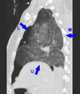

Lung torsion